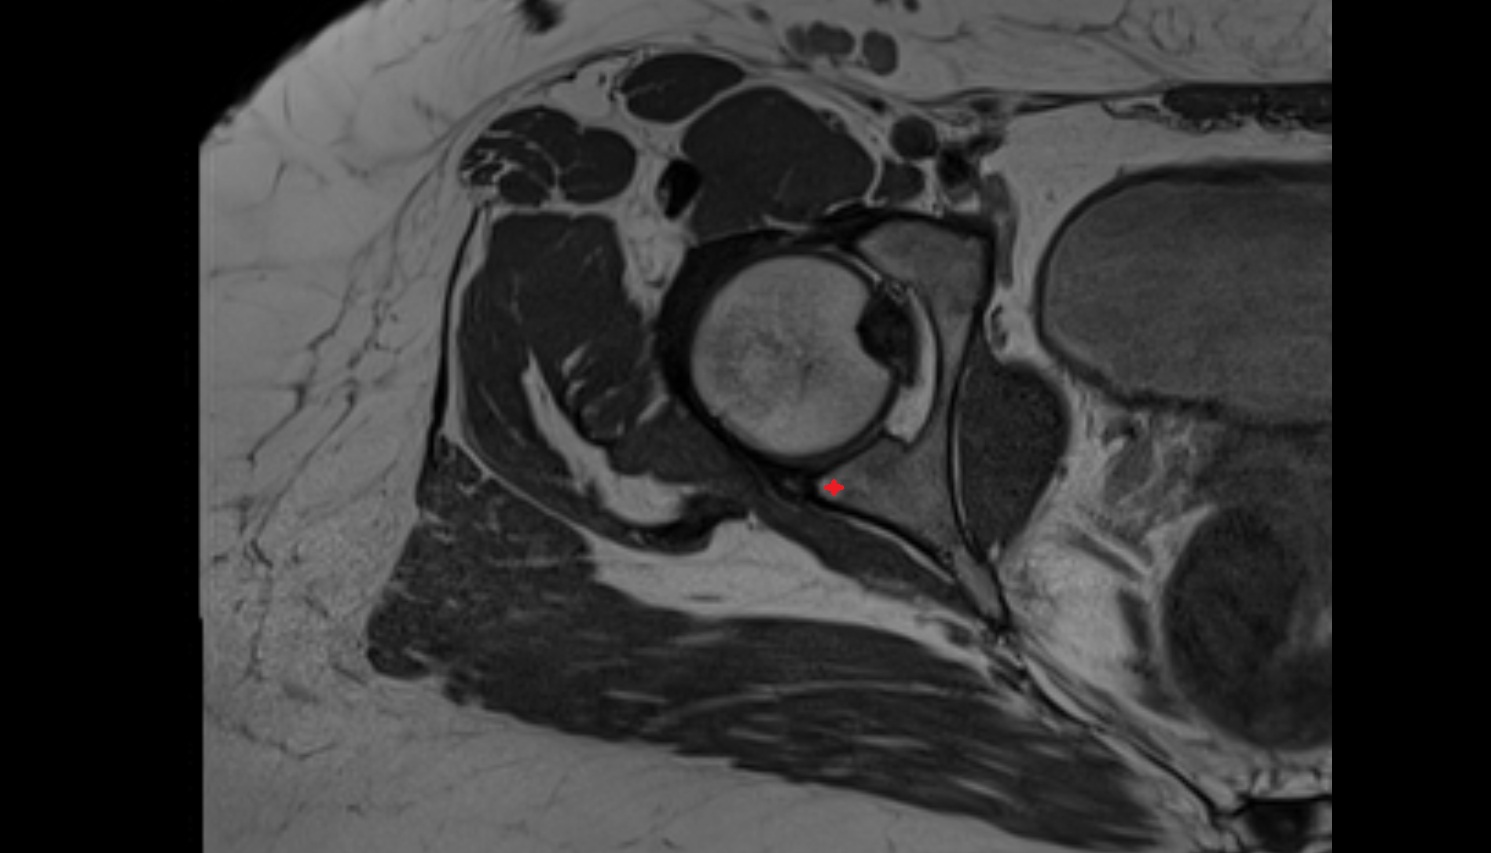

- Head of femur

- Neck of femur

- Acetabular labrum

- Articular capsule of hip joint

- Hip joint